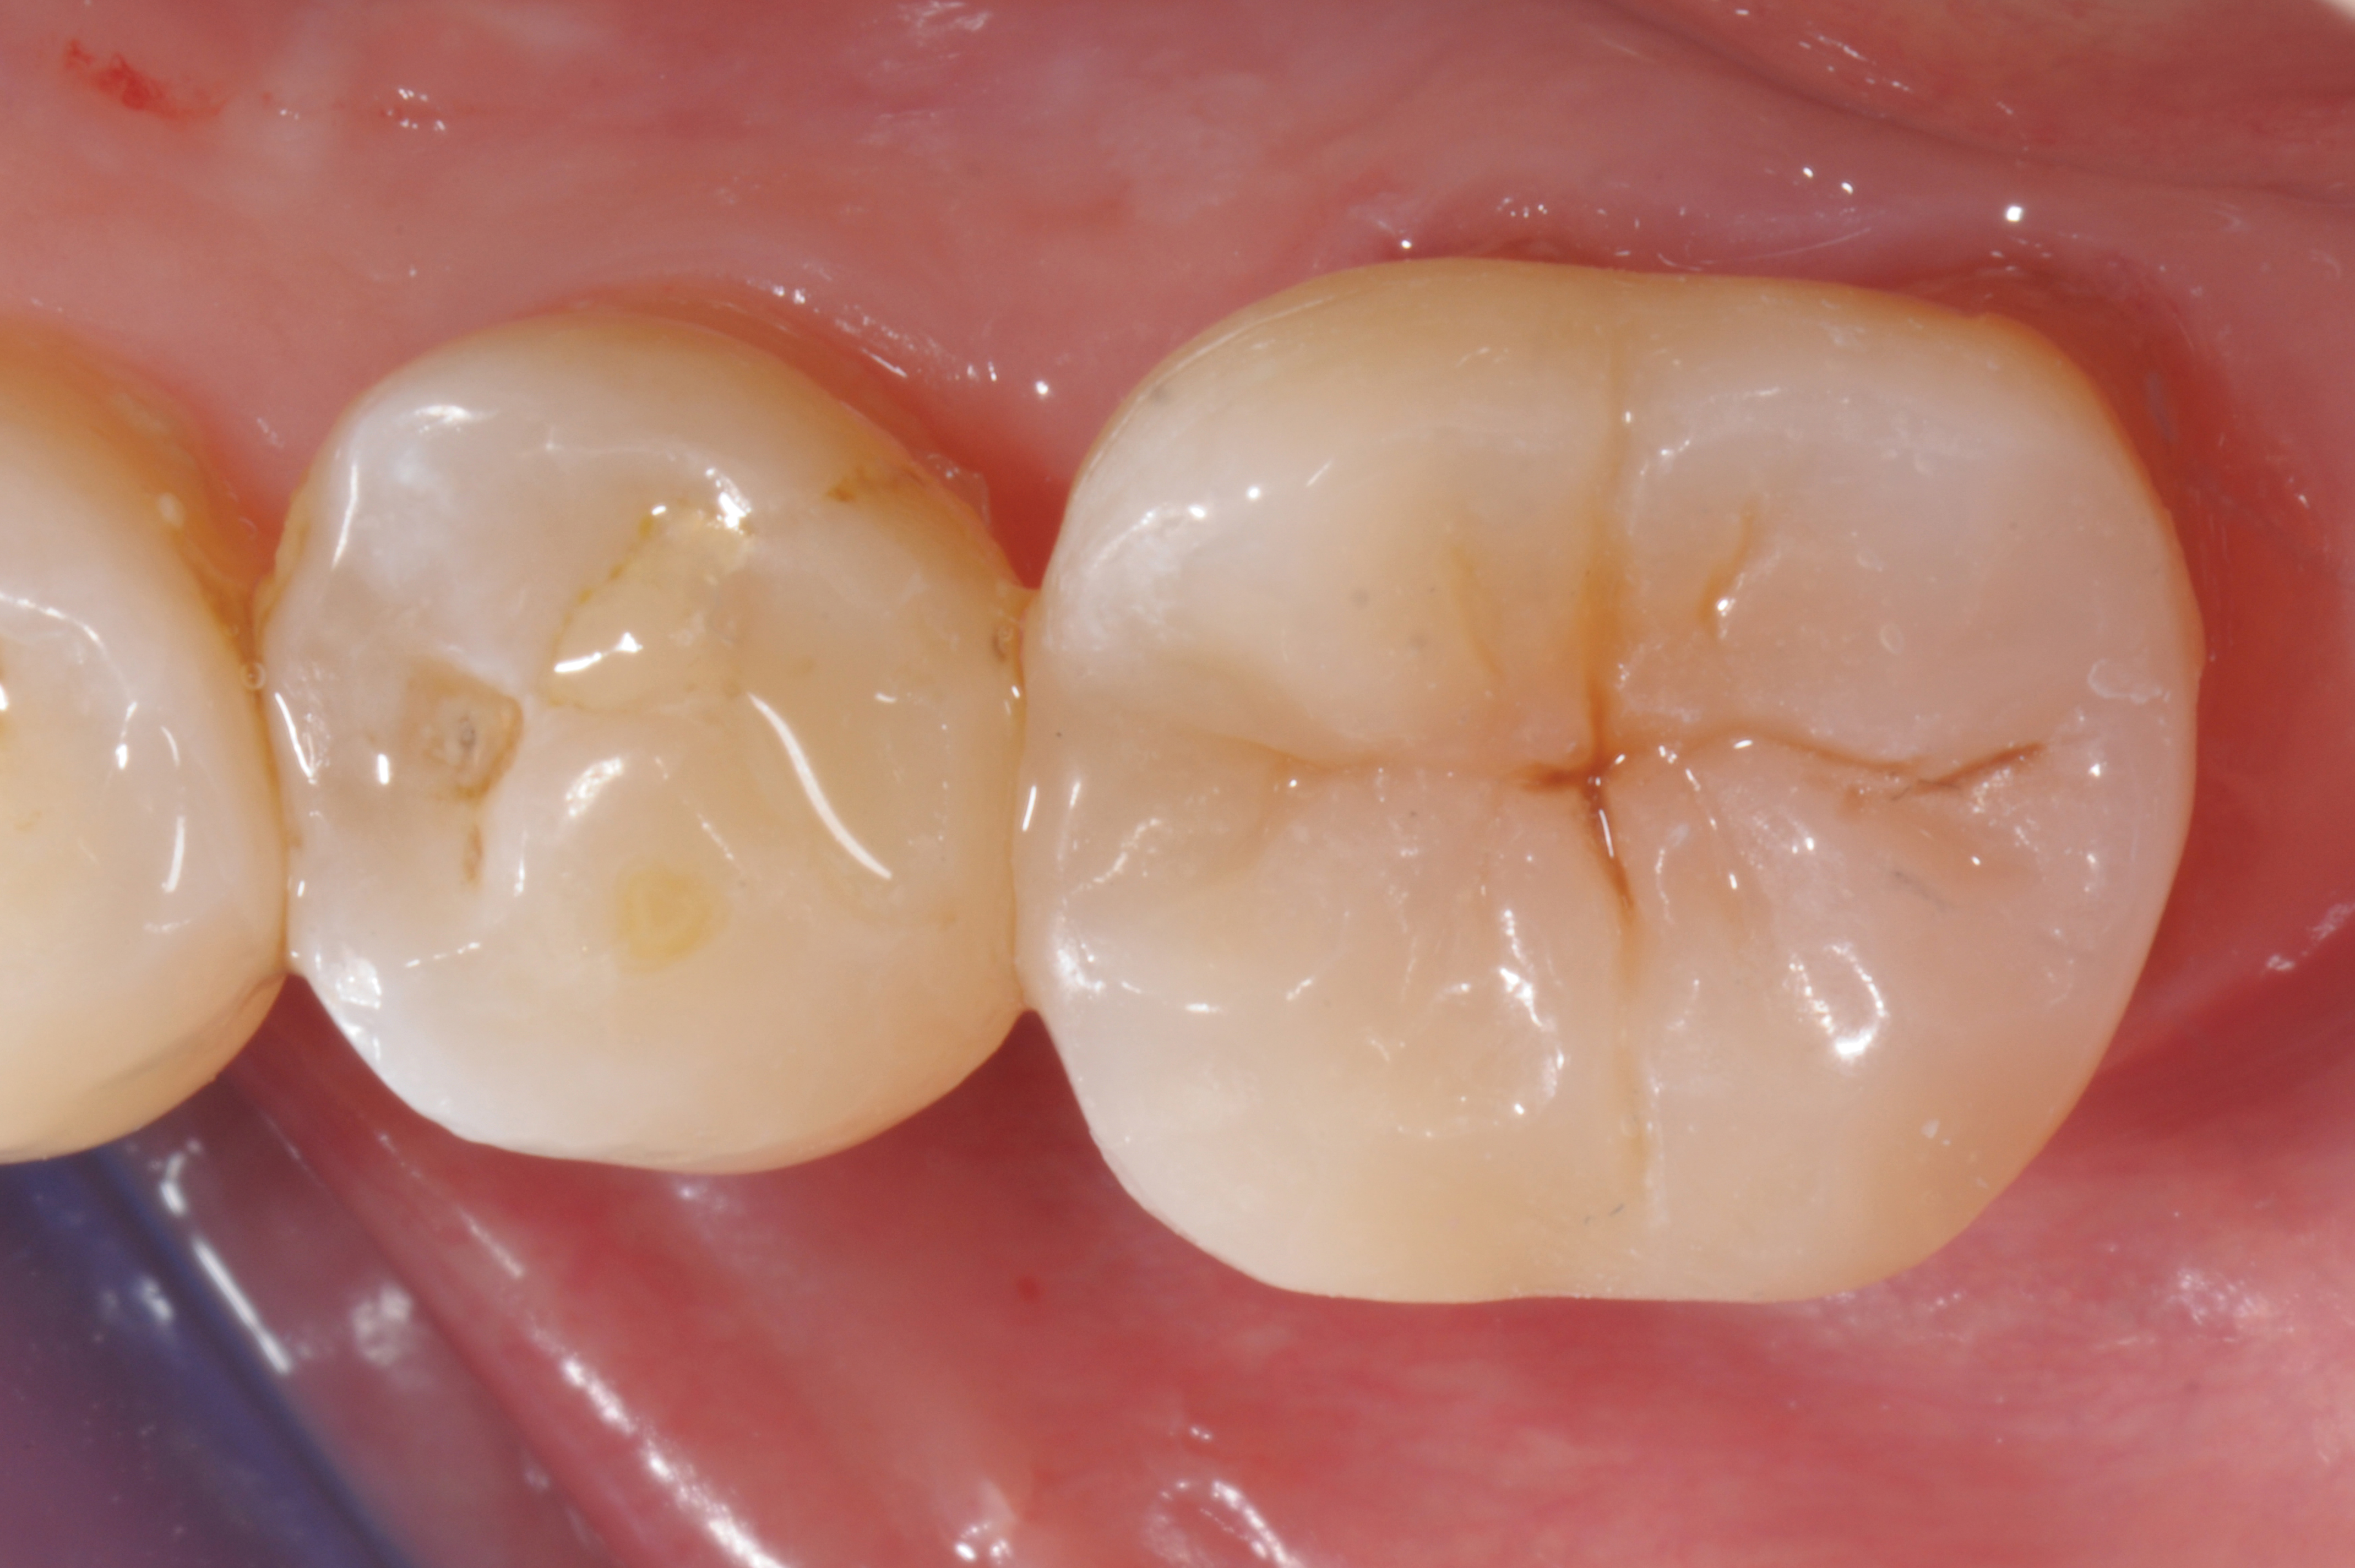

Fig 2. Immediate dentin sealing.

Figure 2

When following a protocol of cementation using an adhesive system, constant rubber dam isolation and careful hand finishing are necessary to provide predictable clinical results (Figure 1 through Figure 4).2